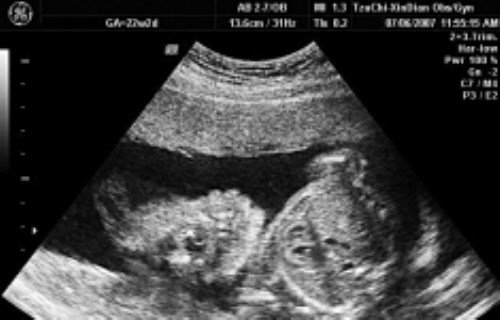

示意圖來源:TVBS

根據《ETtoday新聞雲》報導,彰化曾有一名爸爸,發現高二女兒竟然懷了男同學的孩子,因為藏肚,家人跟老師完全沒發現,直到爸爸發現女兒行為怪怪的,追問之下才發現女兒已經懷孕8個月,當下震驚到不知該如何是好,內心只不斷想著「女兒才高二啊!該怎麼辦?」